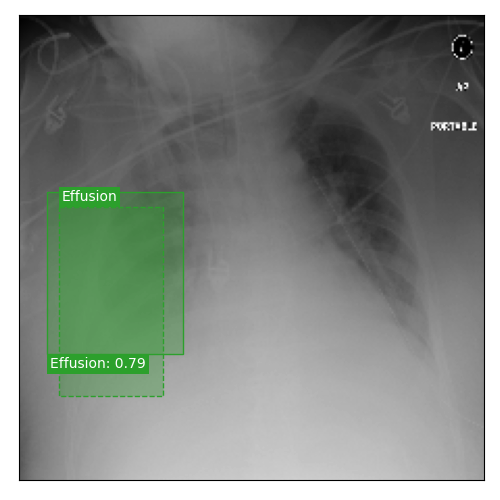

Qualitative Results

As shown in Fig. 4 Loc-ADPD detects cardiomegaly almost perfectly, as it is always exactly localized at one anatomical region. Other pathologies are detected but often with too large or too small boxes as they only cover parts of anatomical regions or stretch over several of them, which cannot be completely corrected using WBF. Detection also works well for predicting several overlapping pathologies. For qualitative comparisons between Loc-ADPD and MIL-ADPD, we refer to Appendix 0.B.